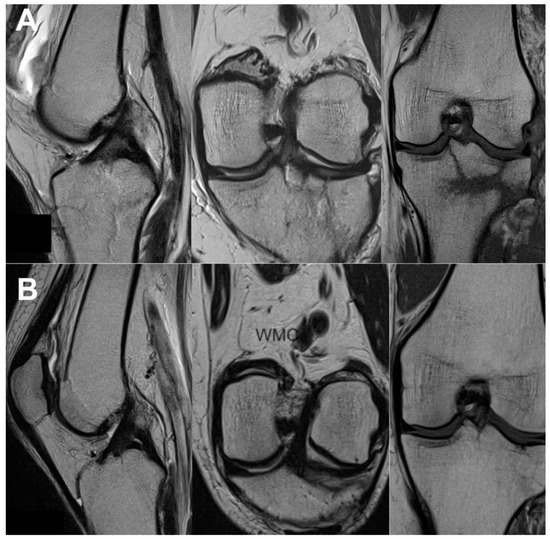

2.4. Imaging Examination

3.3. Imaging Analysis